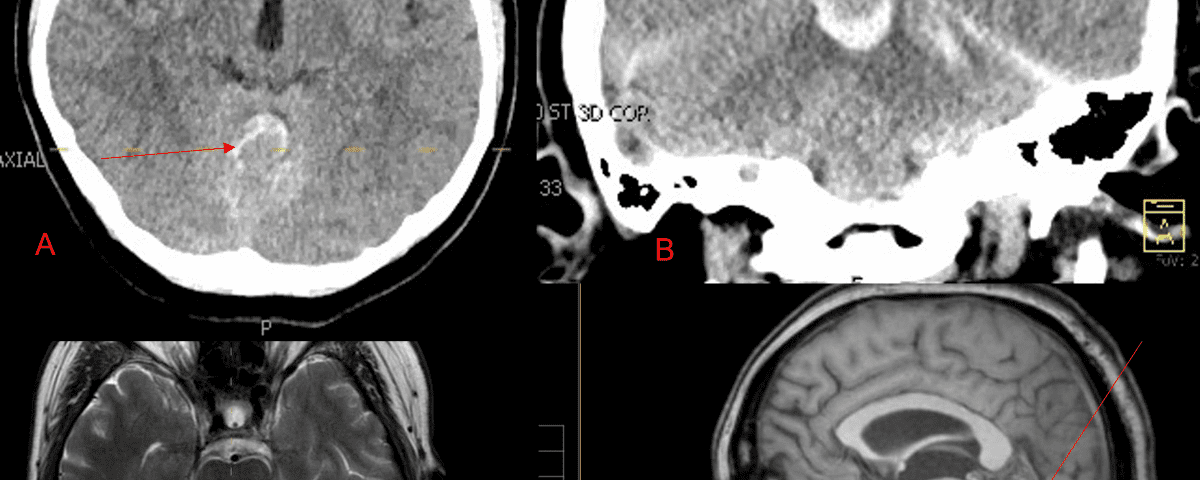

A 55-year-old woman presented with acute onset of severe headache, and possible witnessed seizure. Imaging confirmed intraventricular hemorrhage primarily focused within the fourth ventricle with diffuse subarachnoid hemorrhage within the posterior fossa and along the tentorium as observed on non-contrast CT and MRI of the Brain (Figure 1).

Figure 1. A and B) Non-Contrast CT Axial and Coronal demonstrate large, ruptured Varix/Aneurysm along the Incisura of the posterior fossa which appears to have mixed hemorrhagic components and enhancement on MRI T2 and post contrast imaging (C and D).